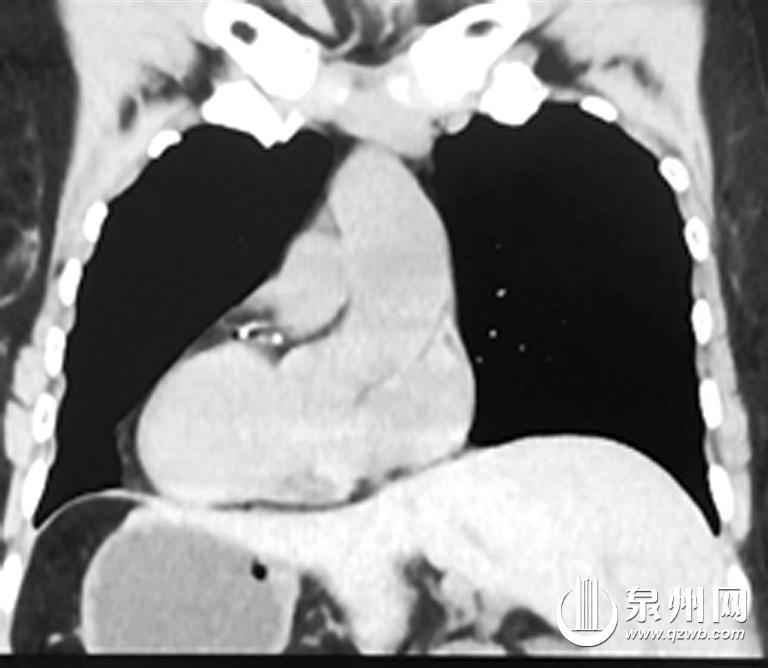

正常人(左)与“镜面人”CT影像对比

泉州市第一医院城东院区胃肠外科主任陈锦萍说:“正常来说,人的心脏在左侧,肝脏在右侧。但该患者从腹部到胸部,所有的脏器全部长反了,也就是所谓的‘镜面人’,即心脏、肝脏、脾脏、胆等器官的位置与正常人相反。在临床中,这种情况的发生率仅百万分之一。”